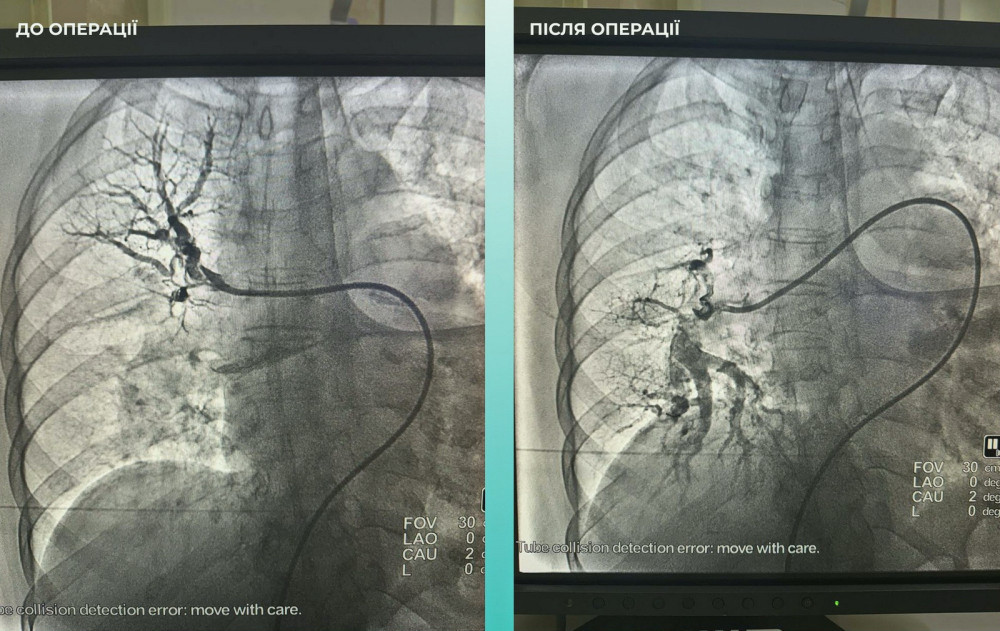

Кроме того, врачи заметили, что пациентка испытывает трудности с дыханием, поэтому провели дополнительное обследование легких. Установлен диагноз тромбоэмболии легочной артерии.

Мультидисциплинарная команда врачей приняла решение провести одновременную тромбоэктомию на мозговых и легочных артериях, что стало критически важным шагом к спасению жизни.

Операция прошла успешно. Пациентка чувствует себя намного лучше: она в сознании и уже начала двигать конечностями.